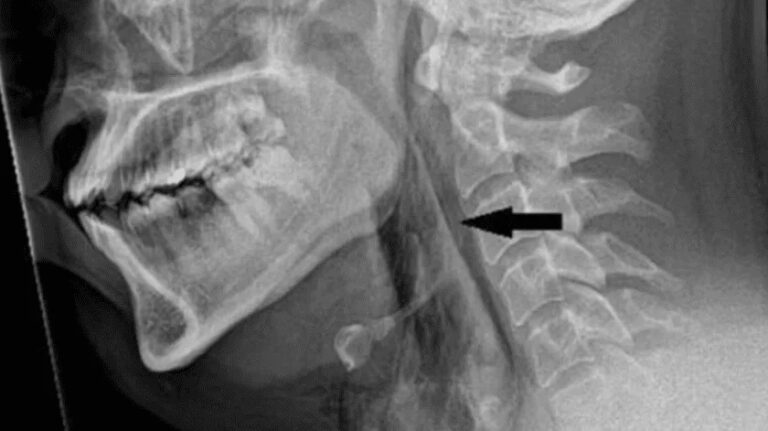

Un joven con antecedentes de alergias sufrió un desgarro traqueal grave después de intentar contener un estornudo. Médicos británicos, indicaron [...]